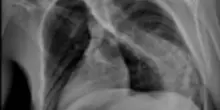

Bimba di 4 anni operata per una rara malformazione al midollo: ora cammina

L’intervento multidisciplinare è stato eseguito all’ospedale materno-infantile Salesi di Ancona. La diastematomielia, con la grave scoliosi sviluppata e i problemi agli arti inferiori, le faceva continuamente perdere l’equilibrio. E sarebbe peggiorata con la crescita